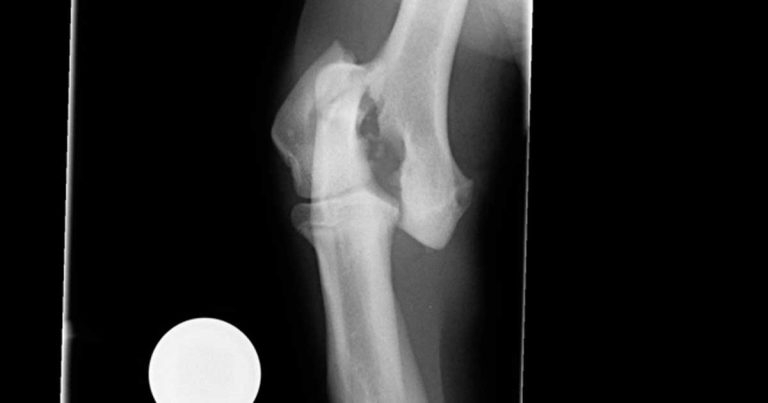

Figure 1. Preoperative craniocaudal radiograph of the right elbow.

As a first step of investigation and treatment, you provide analgesia and perform radiography of the right elbow (Figure 1) under general anaesthesia.

A fracture of the lateral aspect of the humeral condyle is apparent. What would you do next?

The radiograph confirmed a fracture of the lateral aspect of the humeral condyle on the right side. However, the patient’s history is also suggestive of chronic lameness and discomfort associated with the contralateral limb. Further investigations are, therefore, indicated prior to proceeding with surgery.